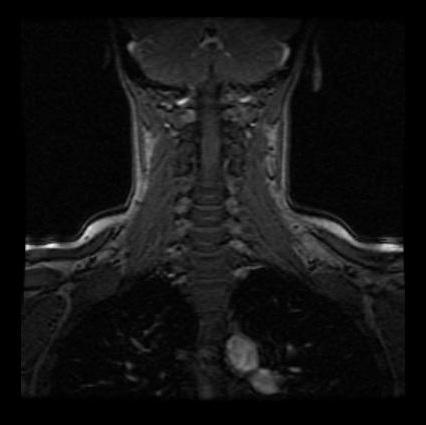

Sie meinten direkt es ist multiple Sklerose. MRT - weiße Flecken. Kleinere weiße Flecken in einem MRT des Schädels müssen nicht immer gleich eine MS bedeuten.

Es gibt sehr oft unspezifische Veränderungen ohne Krankheitswert. Diese Punkte können als nicht identifizierte helle Objekte UBO Bereiche mit hoher Signalintensität HSIA Hyperintensitäten der weißen Substanz und unspezifische Veränderungen der weißen Substanz bezeichnet werden.

MRT - weiße Flecken. Was bedeuten weiße Flecken. Die MRT bringt keine Strahlenbelastung mit sich. Sie meinten direkt es ist multiple Sklerose. Der Leistenkanal im vorderen Bauchraum wird durch Muskelhüllen Faszien gebildet und kann eine Schwachstelle sein. Wenn Ihr Arzt Ihnen mitteilt dass sich auf einem Magnetresonanzbild MRT Ihres Gehirns Flecken befinden könnte. Veränderungen der Muskulatur des Beckenbodens sind sehr gut im MRT abzubilden. Flüssigkeitsansammlungen als weiße Flecken sichtbar. Auf der aufnahme vom 259.

Die Veränderungen müssen immer im Zusammenhang mit der klinischen Symptomatik gesehen werden. Was bedeuten weiße Flecken. Aber es wäre auch möglich dass wenn der weisse Fleck ausserhalb des Knochens ist um die normale Gelenkflüssigkeit handelt. Wenn eine MRT des Abdomens also Bauchraumes auch Abdominal-MRT ansteht handelt es sich in der Regel um sehr gezielte Fragestellungen an Organen. Gestern war ich in einem MRT. Bei der MRT des Beckens handelt es sich um ein bildgebendes Verfahren welches nicht invasiv ist. Es gibt sehr oft unspezifische Veränderungen ohne Krankheitswert.